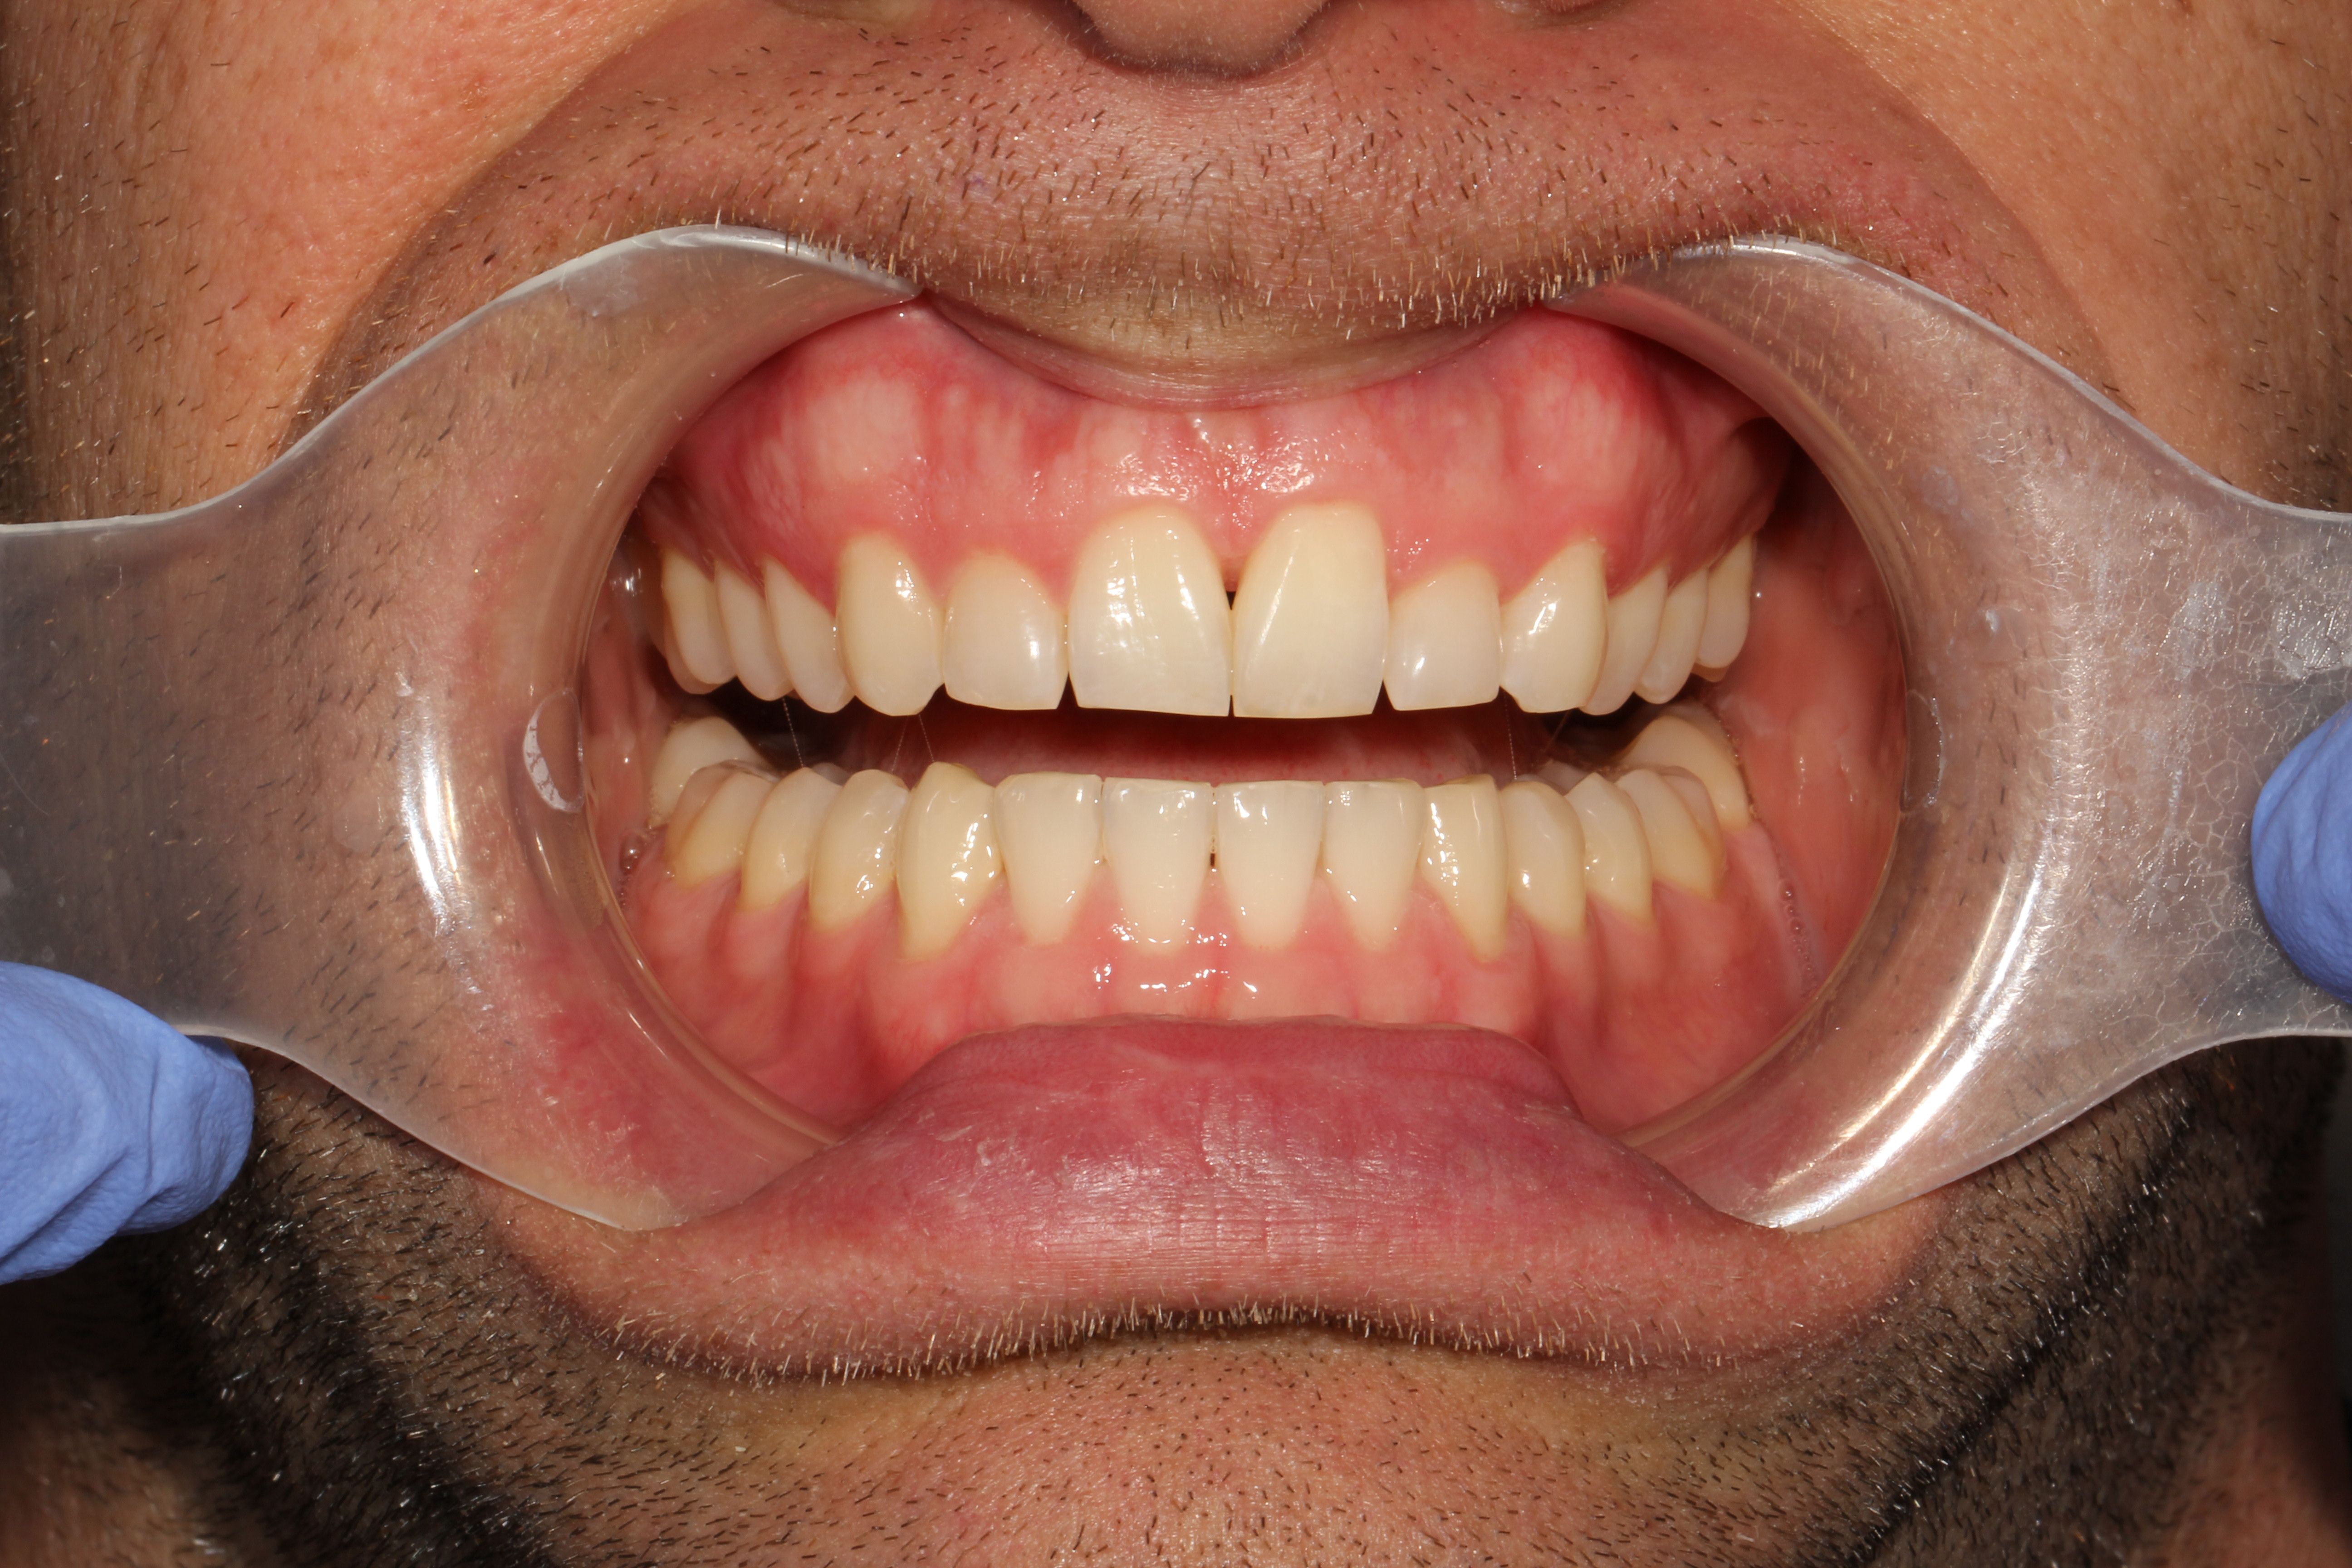

A 32-year-old male patient presented with a chief complaint of rotated tooth 9 and uneven anterior gingival heights. The patient was not interested in traditional orthodontic brackets and wires and decided on clear aligner therapy due to its esthetic and hygienic advantagesUpon reviewing the process with the patient, the decision was made to initiate ClearCorrect clear aligner therapy. The patient consented and the appropriate impressions and photos were submitted to ClearCorrect for a treatment setup.

The treatment goals for clear aligner therapy were focused on rotating tooth 9, extruding tooth 9 and subsequent enameloplasty to even out the maxillary anterior teeth. The patient also had mild Class II molar and canine relationships with crowding and spacing discrepancies in the anterior teeth. The goal with the extrusion of tooth 9 was to move the adjacent bone and soft tissue coronal with the tooth movement. Additional space was needed for the maxillary teeth to accommodate the rotation of tooth 9 into the correct position. Lastly, extra spacing between the lower teeth was to be treated along with the mild Class II malocclusion (Figs. 1-8).

Fig 3: Pre-op (front view) Fig. 4: Pre-op (front view, open)